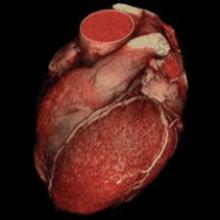

The good news is that hybrid imaging, one of the fastest-growing markets in medical imaging, is an effective tool for noninvasive disease detection, monitoring and therapy. The trouble is that many physicians cannot optimize the use of all the high-volume data generated because their workstations lack advanced visualization applications for rendering 3-D and 4-D images.